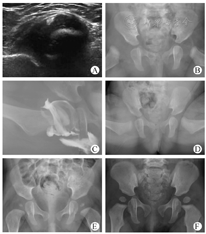

髋关节维持屈髋110°外展55°~60°位,佩戴支具后即刻及前3周每周复查1次Harcke超声,维持支具固定,观察股骨头复位情况及是否存在盂唇嵌顿。若3周内股骨头复位,则每4周复查1次,应用Harcke技术评价髋关节稳定性改善情况,髋关节稳定后更换外展支具固定并应用Graf技术重新分型。如连续2次Graf分型为Ⅰ型,或婴儿满6月龄后骨盆X线正位片显示为IHDI-Ⅰ型,视为髋关节发育转为正常,结束治疗,定期随访。若3周后股骨头仍不能复位,则放弃支具治疗,行基础麻醉下闭合复位,关节造影证实复位成功,判断安全角>45°,屈髋110°外展60°人类位石膏固定。此后每3~4周复查1次,应用Novick超声技术[14]经髋内侧横切扫描,观察头臼对位情况。石膏固定10周后拆除,婴儿年龄低于6月龄则应用Graf技术分型,已满6月龄则摄X线骨盆正位片,若Graf或IHDI分型为Ⅰ型,继续应用外展支具固定8周,结束治疗,定期随访。典型病例见图1。

226髋首诊超声分型情况见表1,其中Graf Ⅰ型162髋于初诊4周后复查仍为Ⅰ型,未予治疗。Graf Ⅱa+型且"稳定"的9髋中7髋"外展正常"并于连续随访中转为Ⅰ型,未予治疗;余2髋因"外展受限"予以治疗。Graf Ⅱa+型且"松弛"、"外展正常"的2髋均转为Ⅱb型,予以治疗。其余分型的53髋均予治疗,则共治疗57髋,25.22%(57/226),平均治疗时间为13周,范围为7~22周。经过治疗的57髋中,有1髋(1.75%)为Graf Ⅲ型且"脱位不可复位",应用Ottobock支具治疗3周后股骨头仍未复位,更换髋人类位石膏固定10周后转为IHDI-Ⅰ型(图2)。余56髋经Ottobock支具治疗,56.14%(32/57)转为Graf Ⅰ型,42.10%(24/57)转为IHDI-Ⅰ型。原"松弛"11髋、"加压可脱位"3髋于治疗后转为"稳定"。原"脱位可复位"14髋中12髋转为"稳定",2髋转为"松弛"。原"脱位不可复位"1髋转为"稳定"。1岁复诊时57髋均为IHDI-Ⅰ型,髋臼指数为(24±2)°,范围在21°~28°。